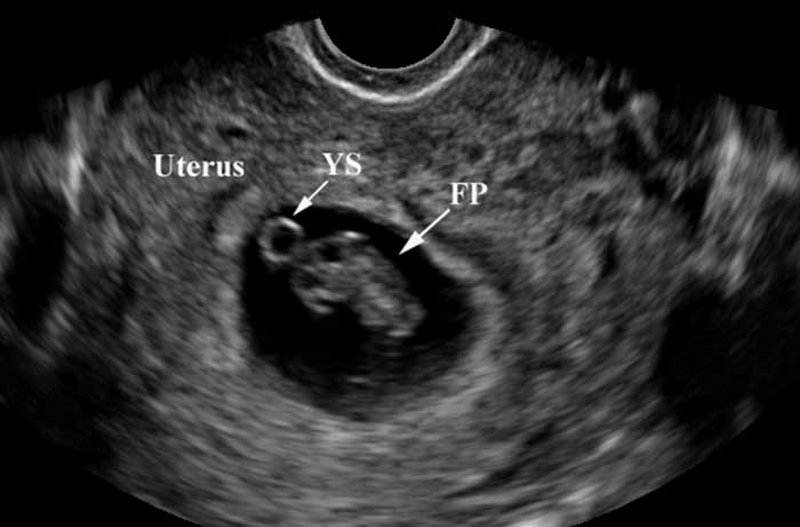

Yolksac hay còn được gọi là túi noãn hoàng, được cấu tạo bởi các nội bì thuộc phôi thai. Đây được coi là một cấu trúc hoàn chỉnh ban đầu của thai nhi. Thông thường, khi bước vào tuần thứ 5 của thai kỳ mẹ bầu sẽ phát hiện được có yolksac thông qua việc siêu âm.

Sự xuất hiện của yolksac còn được coi là sự chuẩn bị cho quá trình hình thành nhau thai ở những giai đoạn sau. Yolksac chứa các protein cần thiết giúp hình thành các tế bào đầu tiên của thai nhi, khi túi ối và phôi thai phát triển thì yolksac cũng tự động phát triển theo sau đó túi noãn hoàng sẽ biến thành cuống noãn hoàng và biến mất để nhường vị trí cho nhau thai.

Thực chất thì việc phát hiện phôi thai hay tim thai thông qua siêu âm không phụ thuộc hoàn toàn vào tình trạng sức khỏe của người mẹ hay sự hình thành, phát triển của thai nhi. Về cơ bản thì đến tuần thứ 7 của thai kỳ, phôi thai sẽ xuất hiện với kích thước khoảng 2mm sau đó theo thời gian nó sẽ to lớn hơn. Nhưng bên cạnh đó, có một số trường hợp khi mang thai đến tuần thứ 7 nhưng chỉ phát hiện có yolksac mà không thấy có phôi thai. Tình trạng này phụ thuộc bởi nhiều nguyên nhân có thể kể đến như: thai nhi phát triển chậm, tính nhầm tuổi thai, trứng bị trống...